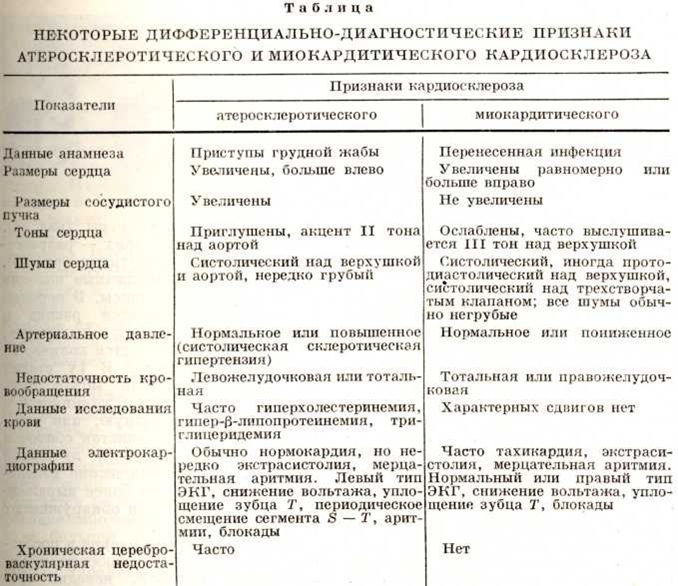

Клинической, проявления миокардитического Кардиосклероз варьируют в зависимости от этиологического форм миокардита, его морфологический особенностей и с известной трудностью дифференцируются с хронический и затяжными миокардитами (смотри полный свод знаний). Для миокардитического Кардиосклероз характерны инфекционные заболевания в анамнезе, наличие хронический очагов инфекции, чаще молодой возраст больных, на ЭКГ изменения диффузного характера или преимущественно правого желудочка; Нарушения ритма и проводимости встречаются чаще, чем симптомы сердечной недостаточности. Дифференциально-диагностические признаки атеросклеротического и миокардитического Кардиосклероз представлены в таблице.